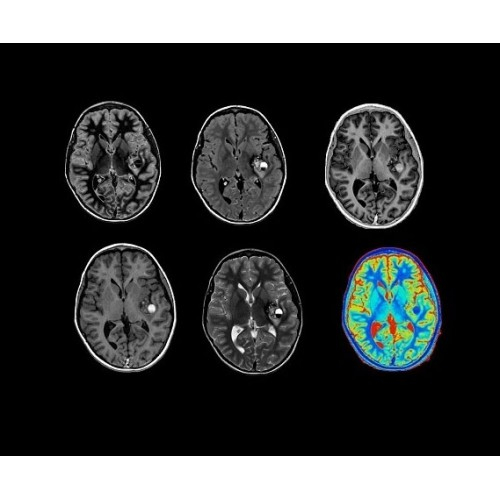

• NeuroWorks — универсальное решение для визуализации анатомии головного мозга, позвоночника, сосудов и периферических нервов с четкой дифференциацией тканей.

• ImageWorks — повысит производительность МРТ благодаря визуализации высокого качества с MAGIC, четкими результатами пост-процессинга с READYView.

• 48-канальная катушка TDI для головы, входящая в базовую комплектацию SIGNA Architect, обеспечивает феноменальную производительность с учетом особенностей каждого пациента. Благодаря гибкому и универсальному дизайну, высокому соотношению сигнал/шум и передовым технологиям визуализации, таким как HyperWorks, учитываются потребности подавляющего большинства пациентов.